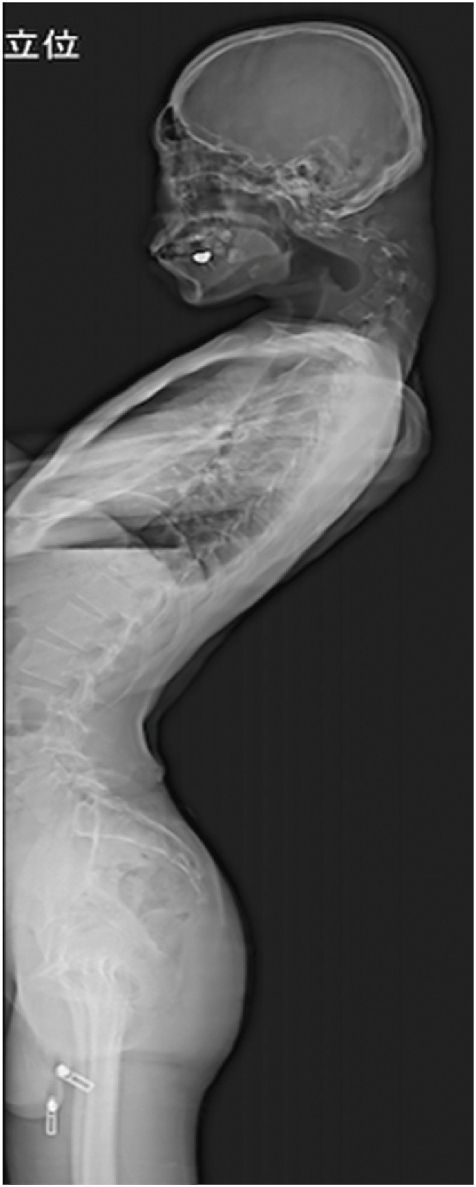

음식을 씹고 삼키기도 어려워 하루에 겨우 한 끼만 먹을 정도로 식사량이 줄어 있었고, 그 결과 걱정스러울 만큼 체중도 감소한 상황이었다.

또 척수 신경 압박으로 양쪽 팔다리에 저림 증상이 나타났고, 특히 왼손의 힘이 약해지는 척수증도 동반됐다.

몇 년에 걸쳐 방에 격리된 상태에서 이러한 습관을 유지했다는 언급으로 미루어 볼 때 환자는 은둔형 외톨이 생활을 한 것으로 추정된다.

그러나 중학교 때 심한 괴롭힘을 당한 뒤 학교를 그만뒀고, 몇 년 동안 방에 틀어박혀 스마트폰 게임에만 몰두하며 지냈다.

논문 저자들은 환자의 심각한 상태의 원인을 기존의 발달장애와 장시간 동안 고개를 숙인 나쁜 자세 습관이 복합적으로 작용한 결과로 추정했다.